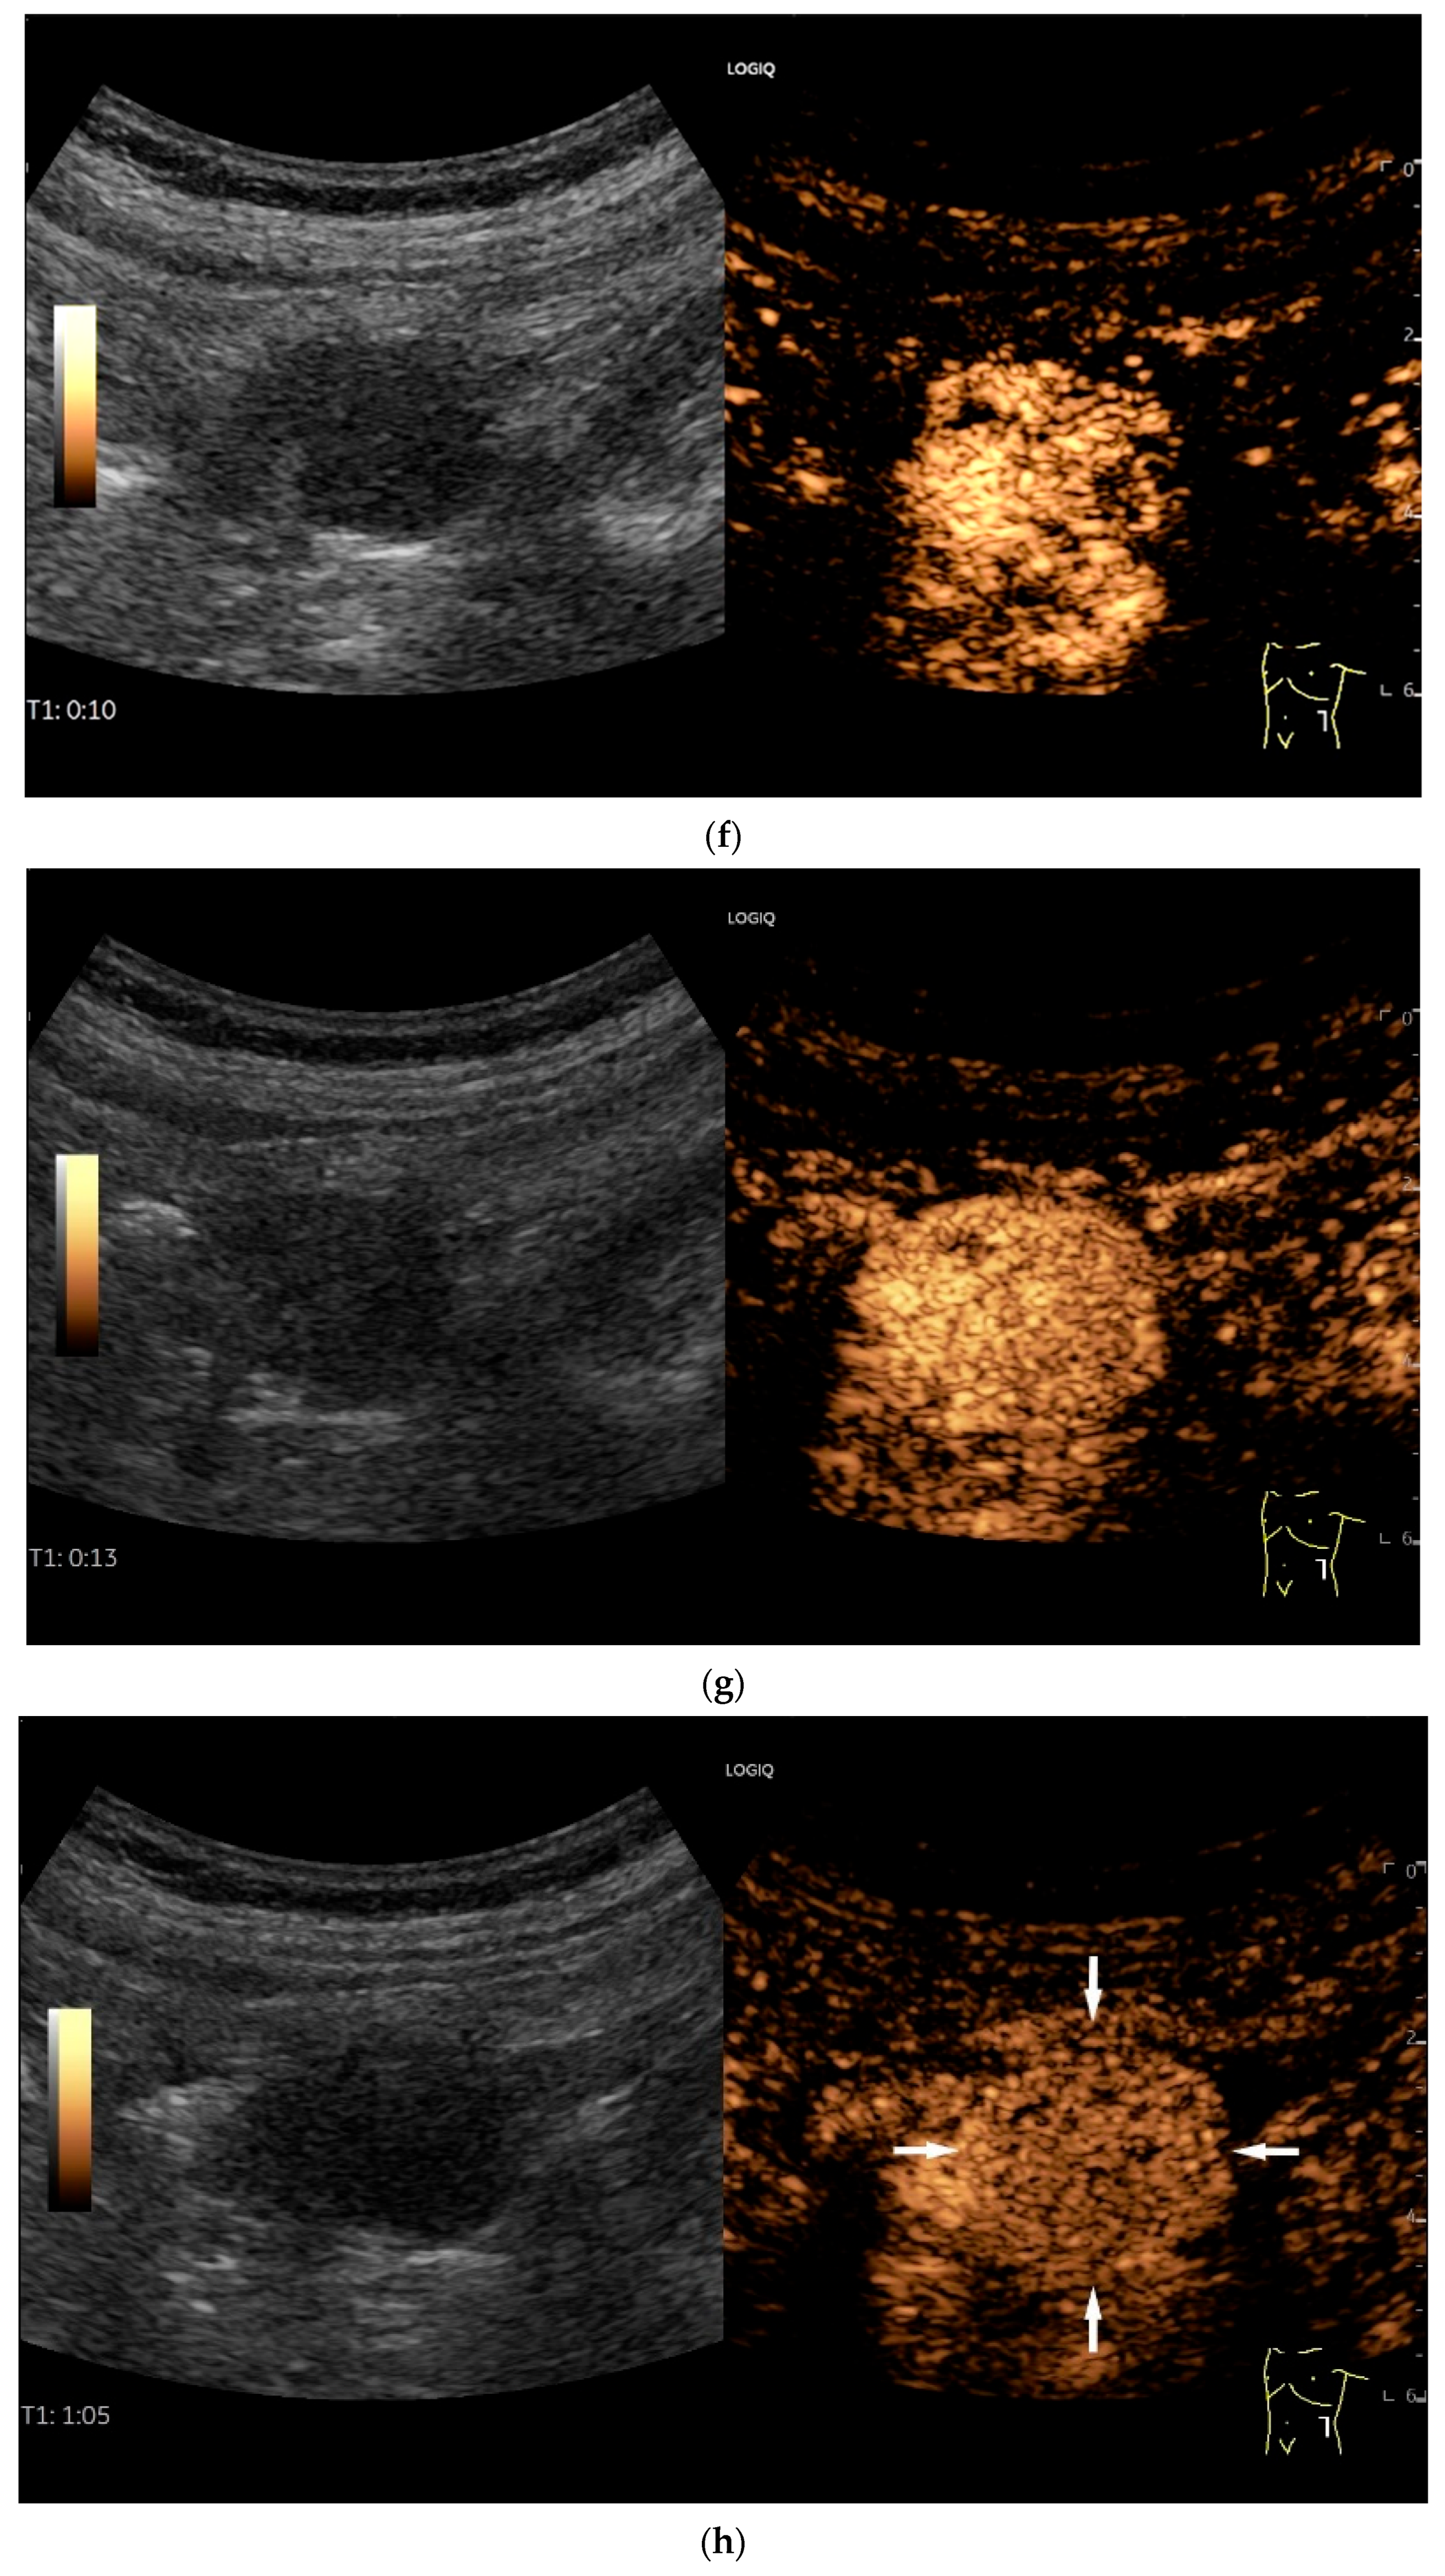

- Zhao, J.Y.; Zhuang, H.; Luo, Y.; Su, M.G.; Xiong, M.L.; Wu, Y.T. Double contrast-enhanced ultrasonography of a small intestinal neuroendocrine tumor: A case report of a recommendable imaging modality. Precis. Clin. Med. 2020, 3, 147–152. [Google Scholar] [CrossRef]

| Neuroendocrine tumor | Small, nodular hypoechoic wall thickenings, mostly in the submucosa with spreading into the other layers. Usually with small vessels on CDI. Regionally enlarged lymph nodes. Multilocular manifestations are possible. |